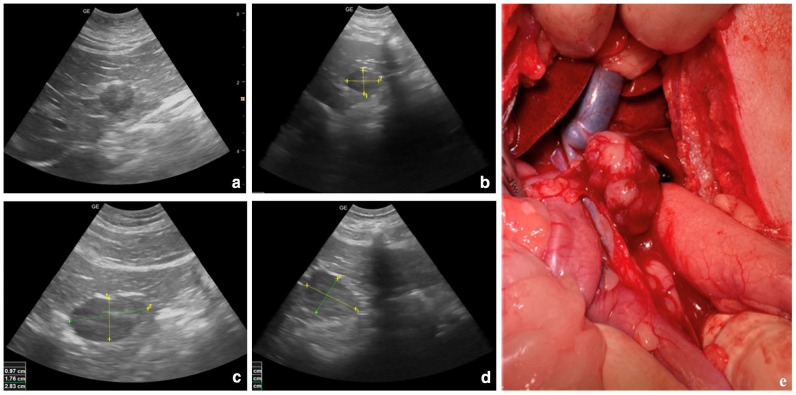

Case summary: Ectopic thyroid tissue is rarely reported in dogs and cats in its prediaphragmatic location and has never been described in the liver. A 15-year-old spayed female domestic shorthair cat was diagnosed by ultrasound with a heterogeneous hypoechoic nodular area in the liver at the periphery of the quadrate lobe. A generic diagnosis of carcinoma was made after ultrasound-guided fine-needle aspiration and cytological examination. The patient underwent staging by CT scan and subsequently underwent hepatic lobectomy. Histologically, a diagnosis of thyroid adenocarcinoma was made, confirmed immunohistochemically using positive thyroglobulin staining; the tumour was suspected to be of metastatic origin. CT scans excluded primary thyroid involvement; in addition, lesions at other sites were not detected. Therefore, a final diagnosis of thyroid adenocarcinoma arising from ectopic thyroid tissue in the liver was made. The cat recovered uneventfully from surgery.

Relevance and novel information: This report describes an unusual case of an adenocarcinoma originating from presumed thyroid ectopic tissue within the liver of a cat. Ectopic thyroid tissue has been rarely reported in both dogs and cats and, to the authors' knowledge, it has never been described in the liver of a cat.